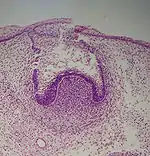

Histologic slide showing a tooth bud.

A: enamel organ

B: dental papilla

C: dental follicle

The tooth germ is an aggregation of cells that eventually forms a tooth.[2] These cells are derived from the ectoderm of the first pharyngeal arch and the ectomesenchyme of the neural crest.[1][3][4] The tooth germ is organized into three parts: the enamel organ, the dental papilla and the dental sac or follicle.